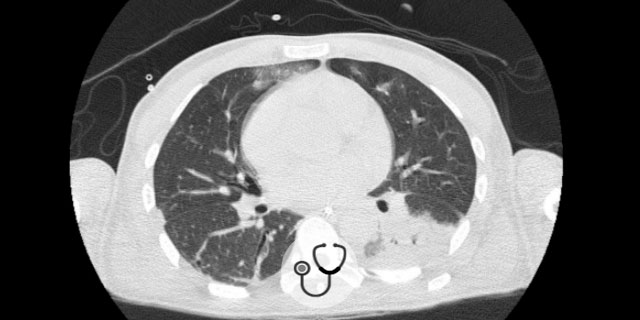

Após oito dias de internação hospitalar, o paciente acordou e foi procedida extubação. Realizada nova coleta de líquor (LCR) com material claro, 3 hemácias/mm3, glicose 56, 72 células/mm3 (60% polimorfonuclear), 75 proteínas mg/dL e baciloscopia negativa. Porém, como mantinha febre e leucocitose, foi realizada tomografia computadorizada de tórax que evidenciou consolidação em base esquerda e peri-hilar no lobo médio direito e segmento superior direito do lobo inferior. A antibioticoterapia foi trocada para meropenem pela possibilidade de infecção nosocomial. As culturas de admissão (líquor, sangue e secreção traqueal) eram negativas.